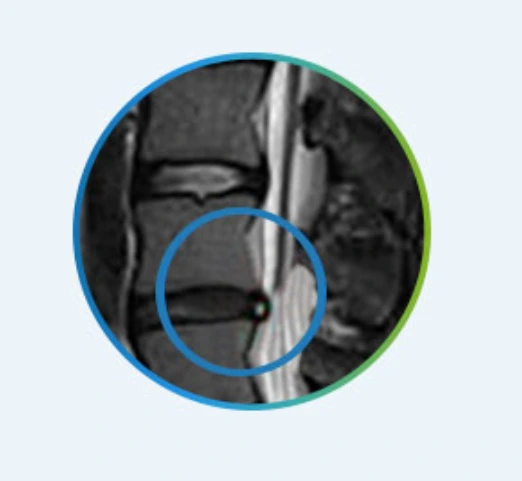

추간공확장술이란 신경 압박으로 발생되는 허리와 다리 통증의 원인을 제거하는 치료법으로 척추관이 좁아지는 척추관협착증에 효과적이지요.

캡처.PNG

추간공확장술은 척수신경이 지나가는 통로인 추간공을 넓혀주는 시술로 비정상적으로 비대해져서 신경을 압박하는 디스크, 인대, 뼈 등의 엉겨 붙은 유착을 미세한 팁으로 박리해 신경을 눌려 압박하는 원인을 없애 주어 통증을 완화시켜 주는 시술이지요.

특수키트로 추간공 내외 측 인대, 특히 척추관의 경우에는 황색 인대의 일부를 절제해 좁아진 공간을 넓히고 신경 및 혈관에 가해지는 압박을 줄여 통증을 완화하고 혈류를 촉진하는 방식입니다. 눌린 신경관을 특수 카테터를 이용해 신경관을 압박하는 결합조직을 제거하는 원리입니다.